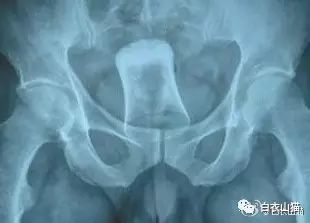

这是做饺子皮用的擀面杖。对,全部塞进去了。你知道怎么看男女吗?看骨盆的角度。